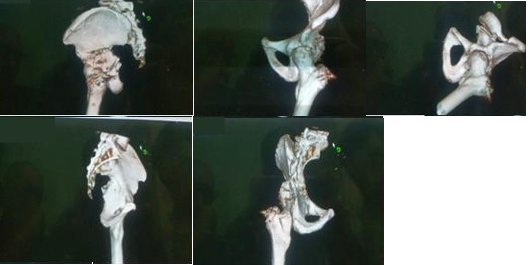

Se obtuvo una reducción de la fractura. (Figuras 4).

El paciente se mantuvo por un periodo de tres meses en descarga tras los cuales comenzó con apoyo parcial con seguimiento radiológico mensual por un periodo de ocho semanas.

Actualmente se encuentra con carga de peso total y continúa en fase de rehabilitación.